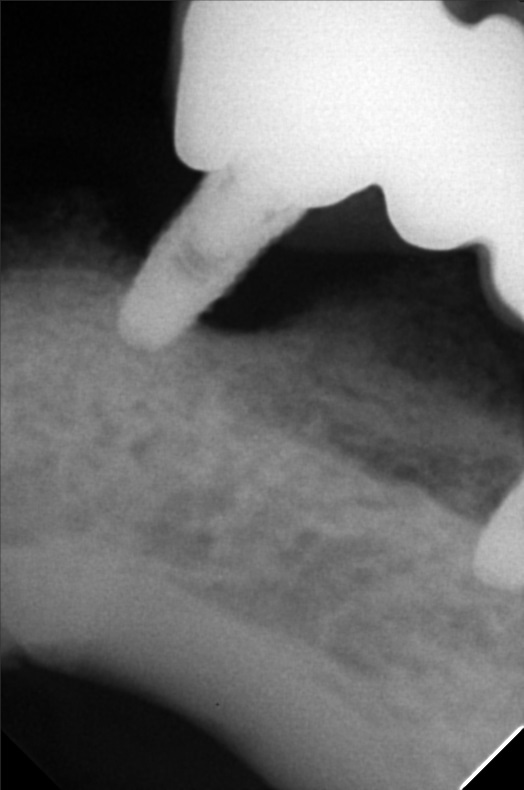

- Procedure